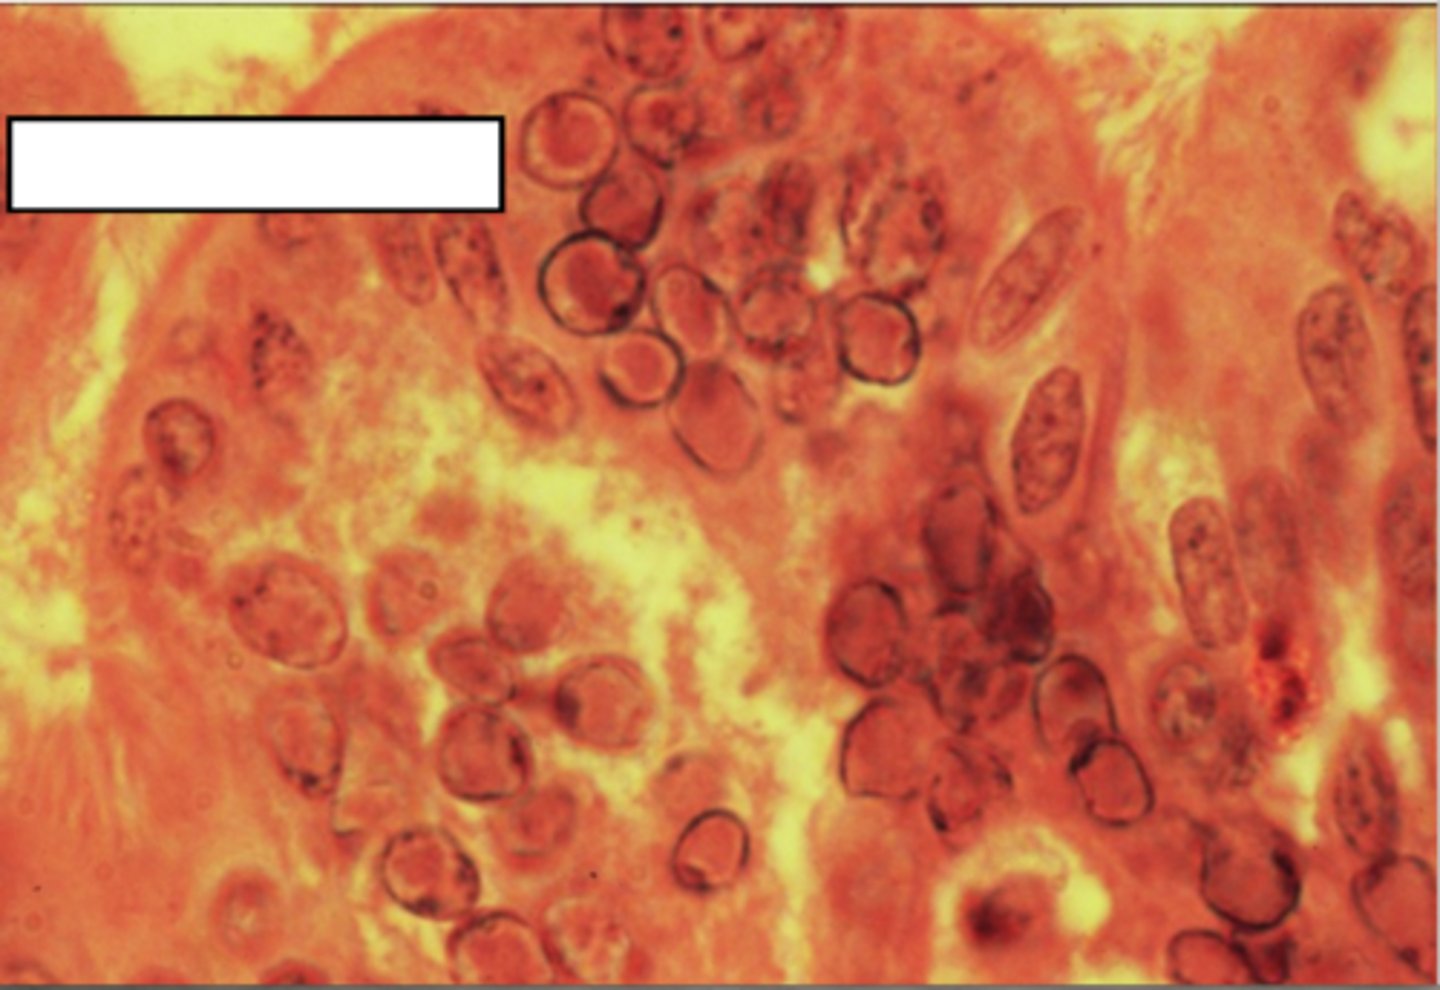

synctia

fusion of multiple host cells into single large cells containing multiple nuclei